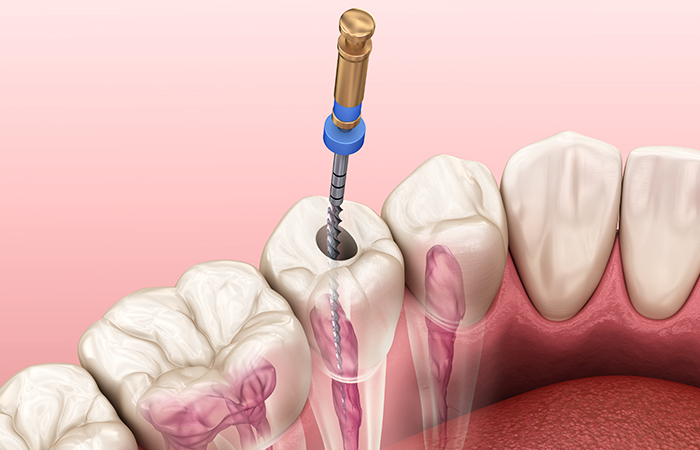

感染した歯髄を除去する

細い針金のような器具(ファイル)を使い、感染した神経を取り除きます。見えない部分の神経までしっかり取り除くため、複数回に分けて除去する場合もあります。

根管内を洗浄・消毒する

感染した神経を取り除いた後は、根管内をきれいに洗浄してから消毒します。根管は細く複雑な形をしているため、時間をかけた精密な処置が必要です。

薬剤を詰めて密封する

根管の中に薬剤をすき間なく詰めるために、根管内を削ったり広げたりして整えます。きれいになった根管内に薬を詰め、細菌が再び入らないようしっかり密閉します。